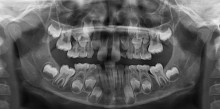

Molaren-Inzisiven-Hypomineralisation (MIH) ist neben Karies eine häufige Erkrankung der Zähne von Kindern und Jugendlichen. Sollten alle konservierenden...

Molaren-Inzisiven-Hypomineralisation (MIH) ist neben Karies eine häufige Erkrankung der Zähne...